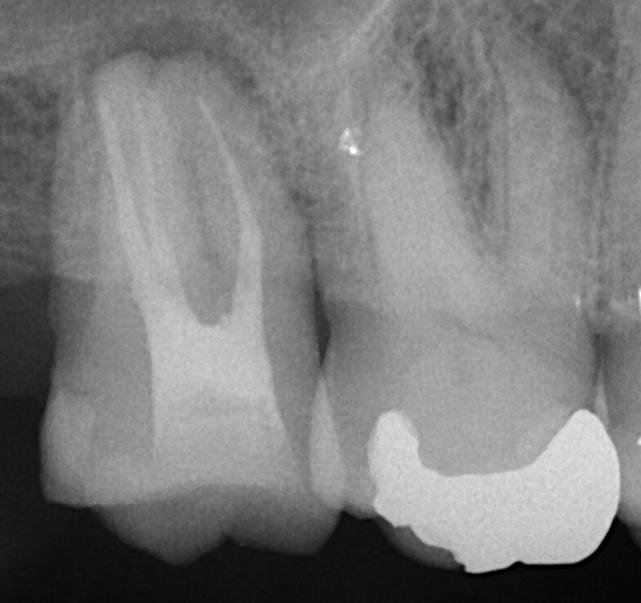

左の歯が根管充填を終えた歯です。3本の棒状の

ものが根管充填剤になります。

根の先を拡大しますとこのように矢印分だけ短く

なっています。

短く見えますが根の先はちょうど矢印の下部分の

場合が多く、レントゲンではこのように写っているのが

丁度いいと思います。